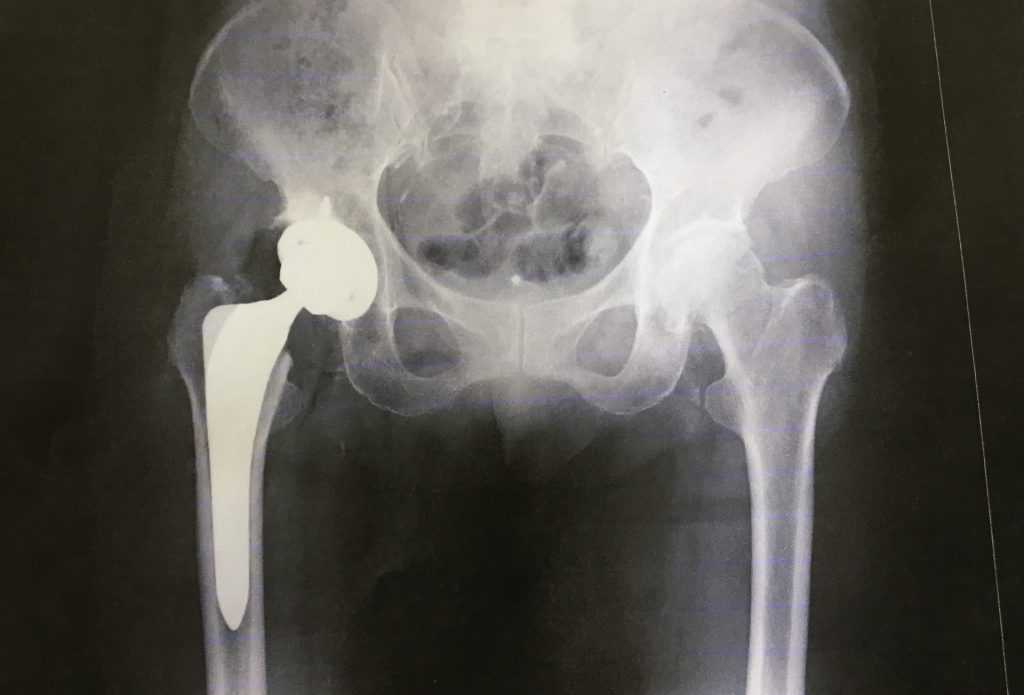

人工股関節置換術とは、病気などで傷ついた股関節を人工の股関節に置き換える手術を指します。

- 1.変形した骨を切除する

- 2.骨の中に人工の股関節を埋め込む

- 3.人工関節を固定する